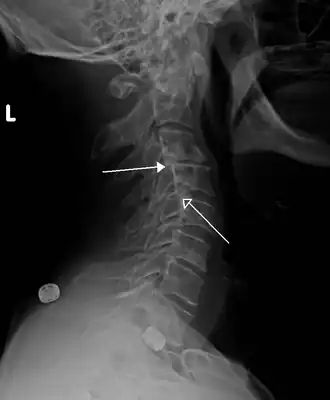

Rétrolisthèses de stade 1 de C3 sur C4 et de C4 sur C5

Un retrolisthesis, rétrolisthèse ou rétrolisthésis (du latin retro, en arrière et du grec ancien ὀλίσθησις, action de glisser), désigne une affection du squelette humain, caractérisée par le glissement vers l'arrière d'une vertèbre par rapport à la vertèbre sous-jacente[1].

Un rétrolisthésis peut être d'origine traumatique (entorse, fracture), rhumatismale (arthrose, arthrite), infectieuse (mal de Pott). Il s'observe le plus généralement au niveau de la partie supérieure de la région lombaire chez des personnes présentant un excès de poids et une hyperlordose (courbure physiologique exagérée de la colonne vertébrale vers l'avant dans la région lombaire)[2].

L'importance du glissement se mesure en prenant une radiographie (de profil). Un rétrolisthésis, dans ses cas les plus graves (lorsqu'il comprime la moelle épinière ou une racine nerveuse) peut entraîner une paralysie partielle (hémiplégie) ou totale (tétraplégie).